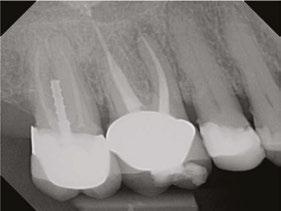

Case 2: Pre-op and diagnosis: A 52-year-old female presented with a chief complaint of pain to hot and cold. Pulpal sensitivity testing on tooth No. 31 revealed a lingering, aching response to thermal testing. A clinical exam revealed a small crack extending from the occlusal resin over the distal marginal ridge. Probing depths around No. 31 were all <3 mm. No. 31 was diagnosed symptomatic irreversible pulpitis with symptomatic apical periodontitis. A pre-op small FOV CBCT revealed No. 31 to have a C-shaped canal morphology. Two treatment options were discussed with the patient: 1) Tooth No. 31 non-surgical root canal therapy or 2) No. 31 extraction. The patient elected No. 31 non-surgical root canal therapy (NSRCT). Treatment: No. 31 NSRCT, the patient was anesthetized with 68 mg Lidocaine with 0.034 mg EPI via IAN and 68 mg Septocaine with 0.017 mg EPI via buccal Infiltration. Rubber dam isolation was utilized, and access was prepared. Due to the C-shaped canal morphology, only two canals could be identified. Prior to placement of the SoundSeal platform, a small amount of bonding agent was placed over the crack along the distal marginal ridge and distal portion of the pulp chamber. The SoundSeal platform was securely placed to create a vacuum seal. The two canals were negotiated to achieve patency by alternating rotary instrumentation and the GentleWave CleanFlow Procedure Instrument for 30-40 seconds to thoroughly debride the internal anatomy. The mesial canal was instrumented to a Master Apical File of 20/.04, while the distal canal to a 25/.04 Master Apical File. Due to the larger and more irregular canal morphology of the distal canal, various-sized gutta-percha cones were used to gauge the size to be used for obturation. The mesial canal was obturated with a Sealer-based obturation method with High Flow BC Sealer and a single 20/.04 master cone. The distal canal was obturated with High Flow BC Sealer and Warm Vertical Compaction. With the aid of the GentleWave and the CleanFlow Procedure Instrument, the C-Shaped canal anatomy was more deeply cleaned, pulp tissue more thoroughly removed, and this case was completed in a single visit which would have been much more difficult to accomplish with traditional endodontic therapy.

10 Endodontic Practice US Volume 17 Number 1 COVER STORY

int the C-shaped main canal. 3D.The obturated enamel of lined canals with Biodentine. The radiopacity is similar to that of dentin. 3E. Healing of the periapical lesion in the 3-year follow-up and continued root formation

Figures 3A-3E: 3A Periapical radiograph of the dens in dente. It is impossible to determine the accurate source of infection. 3B. Hedstrom file in the invagination. 3C. Files